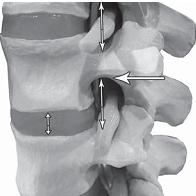

На фото № 10 макета позвоночника наблюдается нормальное взаимоотношение суставных поверхностей дугоотростчатых суставов, в норме высота межпозвонкового диска и межпозвонковых отверстий.

На фото № 11 макета позвоночника наблюдается смещение (подвывих) суставных поверхностей дугоотростчатых суставов. Подобное смещение, как правило, происходит вследствие развития дегенеративно-дистрофических процессов в межпозвонковом диске. При этом уменьшается высота диска, сужается просвет фораминального отверстия (межпозвонкового), что может способствовать ущемлению спинномозговых корешков (нервов) и сосудов.